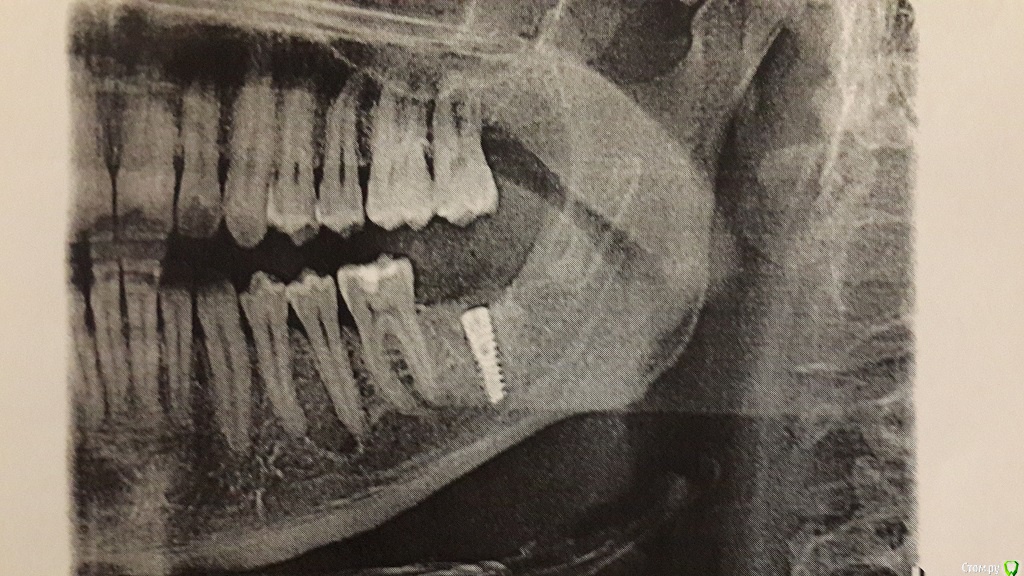

vavan Опубликовано 26 августа, 2015 Поделиться Опубликовано 26 августа, 2015 (изменено) Добрый день.Была произведена имплантация нижней 7-ки. Во время операции при установке импланта, когда он был уже почти до конца закручен, кратковременно ощущалось покалывание щеки и губы.После того как отошла анестезия все было хорошо чувствительность полностью вернулась, но на следующее утро онемела часть губы. Потеря чувствительности не полная, примерно как когда отлежишь руку. Иногда на онемевшем участке ощущается легкое покалывание. Сейчас четвертый день после операции улучшения чувствительности нет. Посмотрите пожалуйста снимок. Это нормальное явление и само пройдет, или необходимо менять имплант на более короткий? Область потери чувствительности обвел красной линией (ошибся когда рисовал,правильно будет то же самое только с другой стороны) Снимок сделанный после имплантации Изменено 26 августа, 2015 пользователем vavan Ссылка на комментарий

Acidrocker Опубликовано 28 августа, 2015 Поделиться Опубликовано 28 августа, 2015 К сожалению, по данной ссылке открывается только панорамный реформат, но, судя по нему, имплантат задевает нерв. Поддерживаю мнения, высказанные выше, не стоит тянуть время.http://s61.radikal.ru/i174/1508/fb/34009009b76c.png Ссылка на комментарий